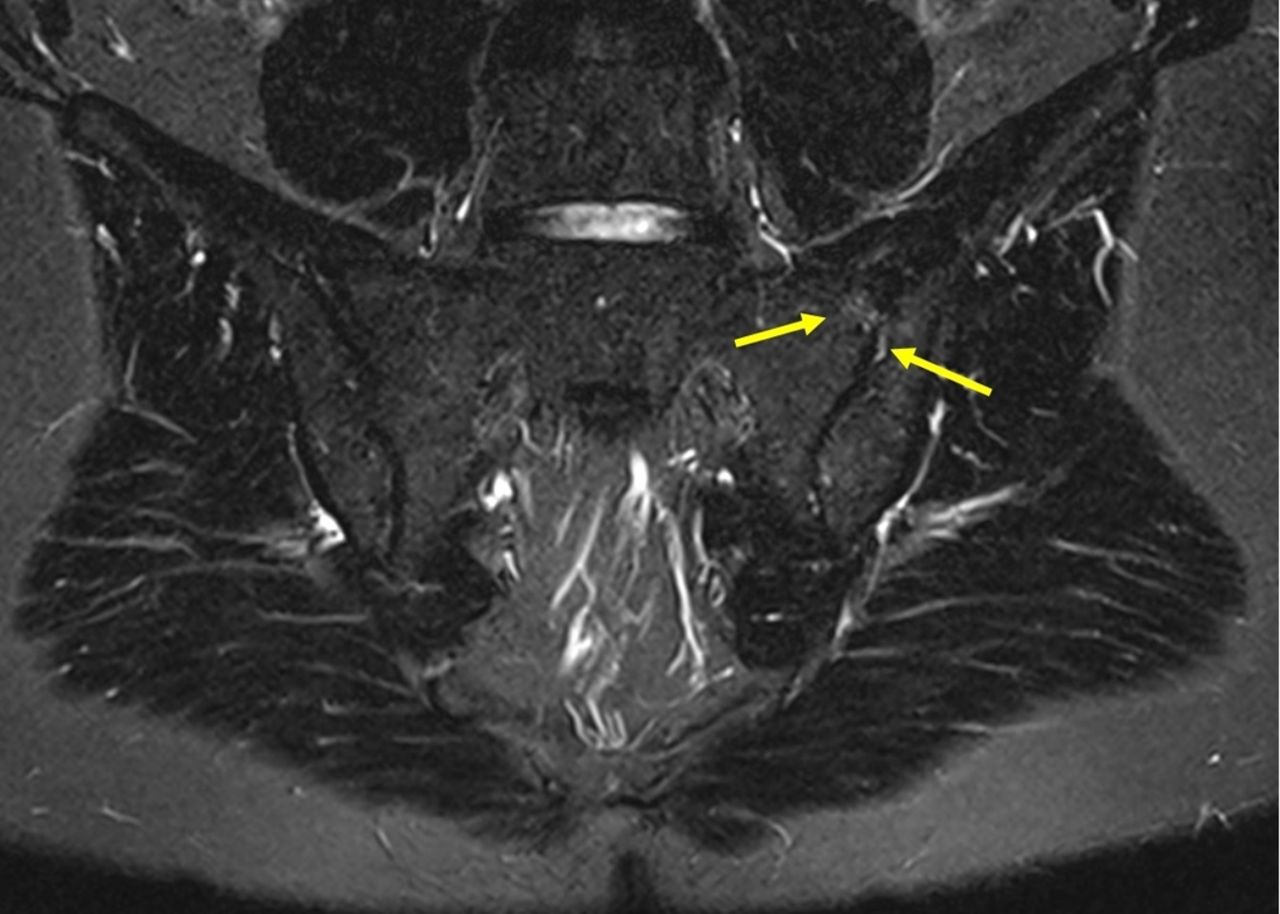

Mri For Diagnosis Of Axial Spondyloarthritis Major Advance With Critical Limitations U2018not